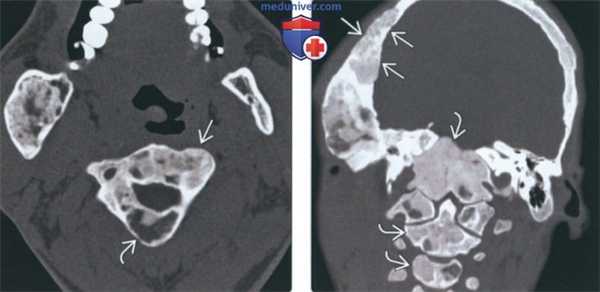

о Синдром Мазабрауда: сопутствующие миксомы мягких тканей![Лучевая диагностика фиброзной дисплазии шейных позвонков]() (Слева) На аксиальной КТ в костном окне у пациента с полиостотической фиброзной дисплазией определяется «чистое» склеротическое поражение боковой массы С1, обнаруженное случайно.

(Справа) На аксиальной КТ без КУ определяется поражение С2 с различной внутренней структурой. Тело и левая невральная дуга вздуты. Большая часть патологического очага имеет плотность «матового стекла». Также определяется очаговый склероз видны маленькие кистозные участки.2. Рентгенография при фиброзной дисплазии шейных позвонков:

о КТ: срезы толщиной 1-3 мм![Лучевая диагностика фиброзной дисплазии шейных позвонков]() (Слева) На аксиальной КТ в костном окне у пациента с полиостотической фиброзной дисплазией определяется поражение С2 и нижней челюсти. Поражение краниофациальных структур типично для полиостотической формы. Определяется характерное вздутие пораженных костей, участки «матового стекла» смешаны с рентгенонегативными очагами.

(Справа) На корональной КТ в костном окне у пациента с полиостотической фиброзной дисплазией трабекулы в большей части пораженных костей замещены матриксом с плотностью «матового стекла» и не видны. Истончение замыкательных пластинок костей черепа - характерный признак.в) Дифференциальная диагностика фиброзной дисплазии шейных позвонков: 1. Аневризматическая костная киста: